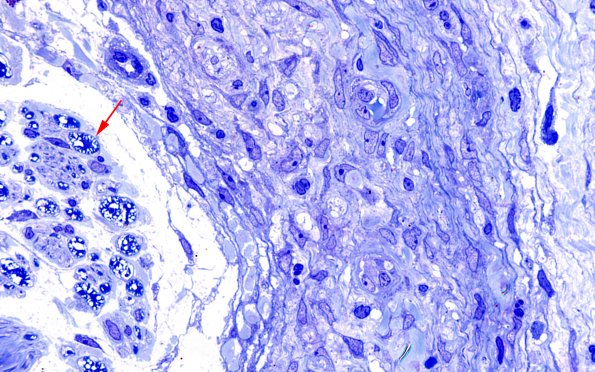

Washington University Experience | PERIPHERAL NEUROPATHY | 19 TRAUMATIC INJURIES | 25I3 Nerve Trauma (Case 25) Plastic 100X 4 copy

Higher magnification images showing the endoneurial content of myelinated axons (arrow) with marked neurokeratin artifact exaggerated by paraffin extraction and subsequent processing. The perineurium shows no axons or mini-fascicles. (Plastic sections)